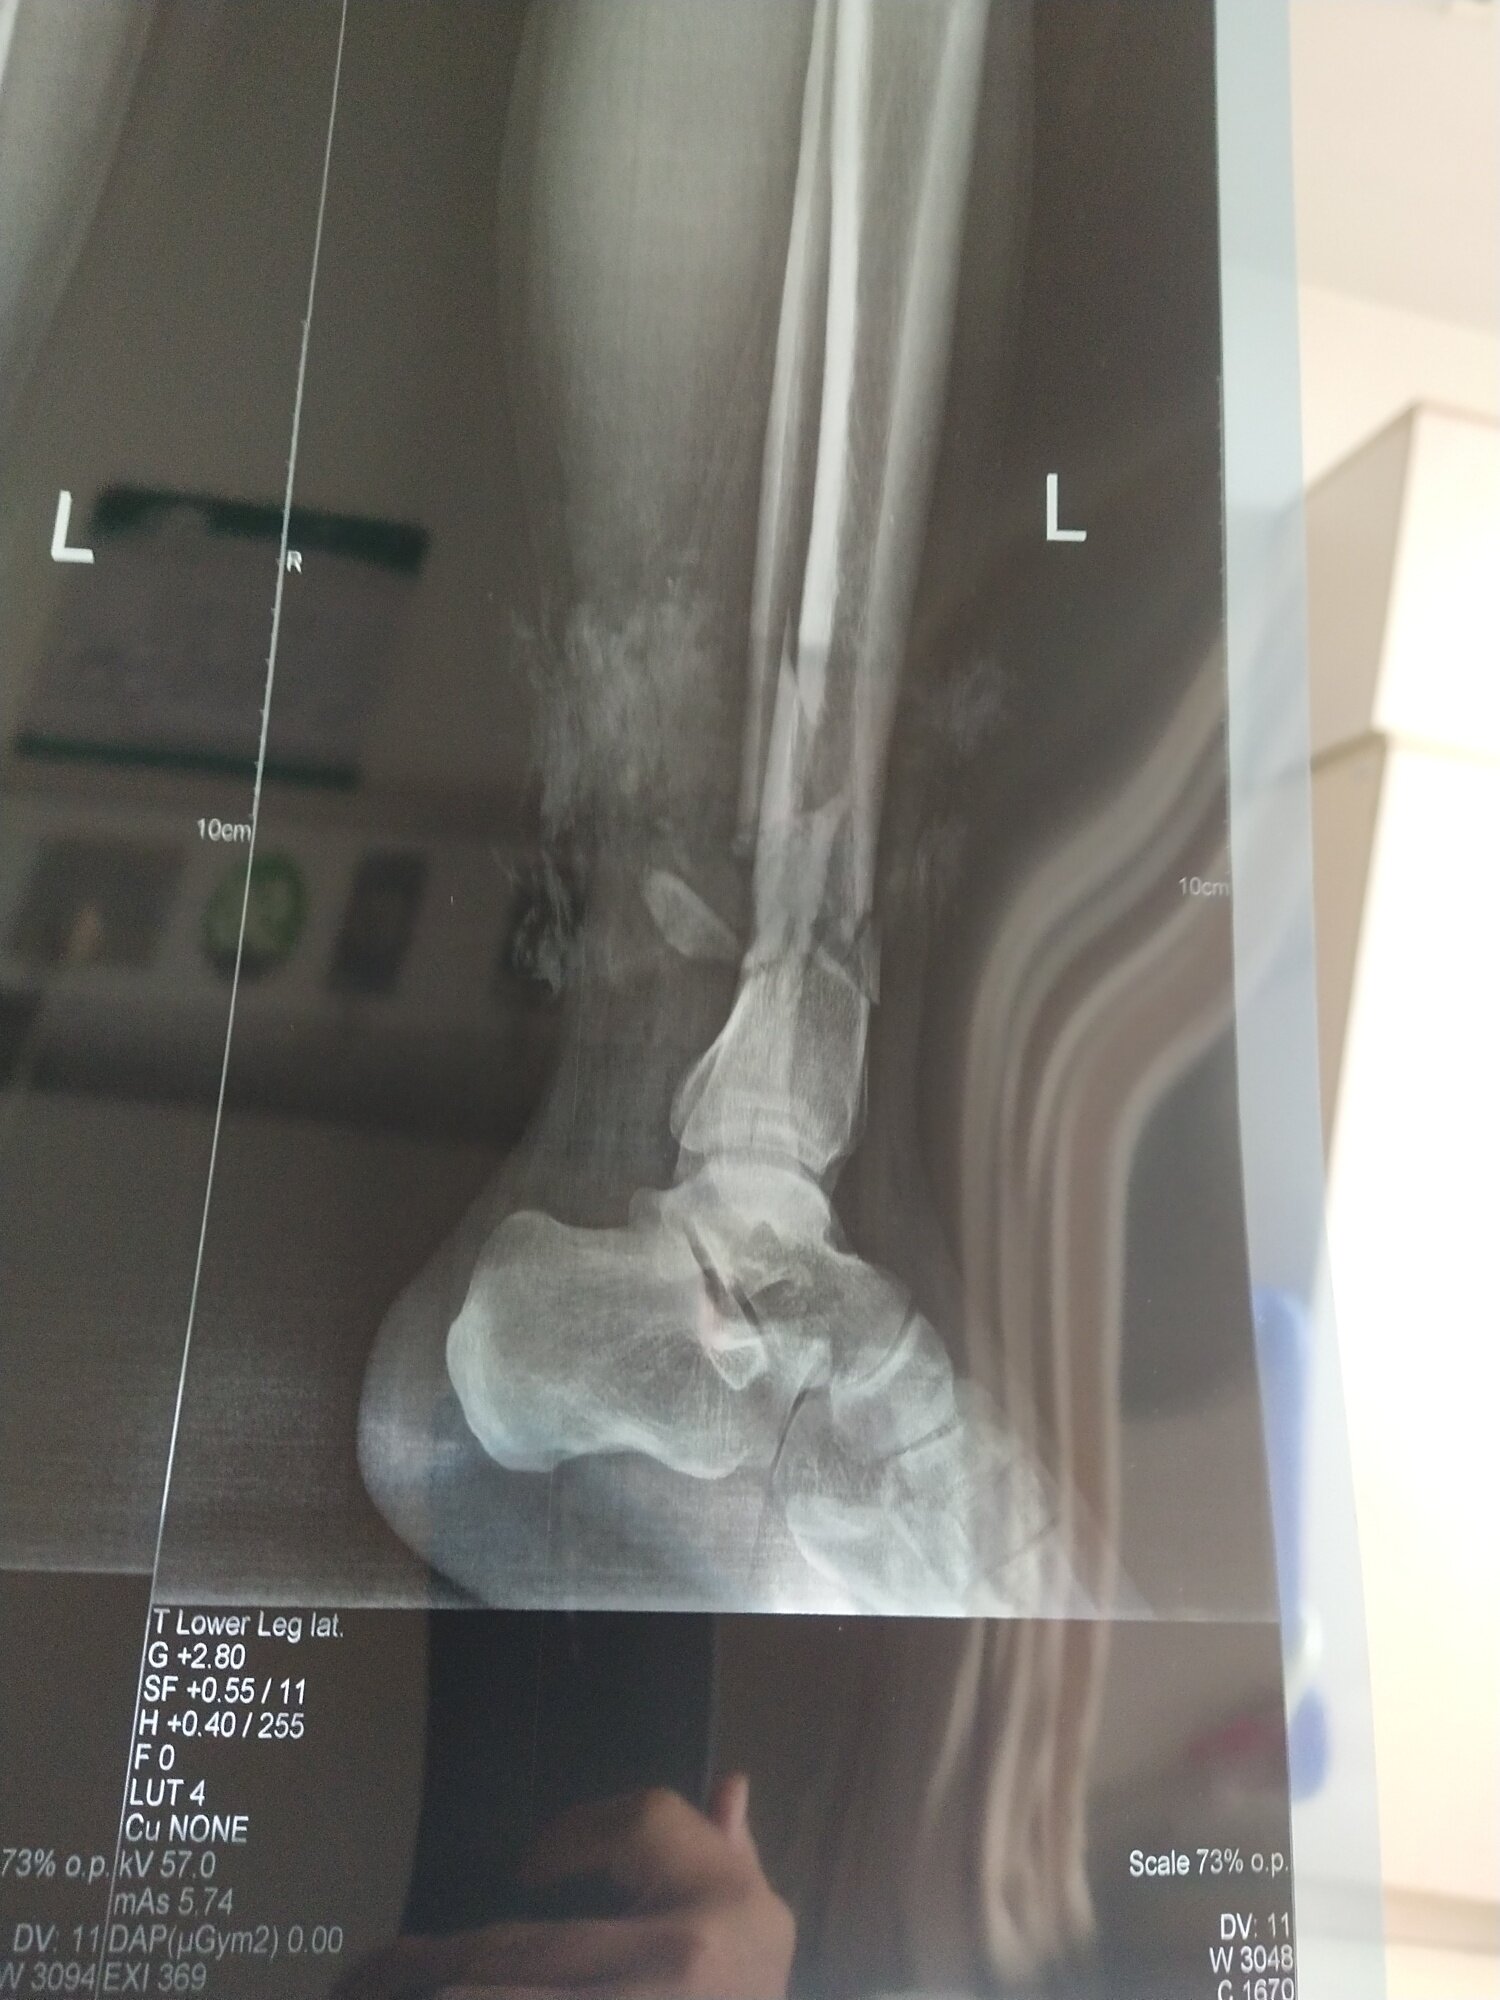

小问题。看看我这个